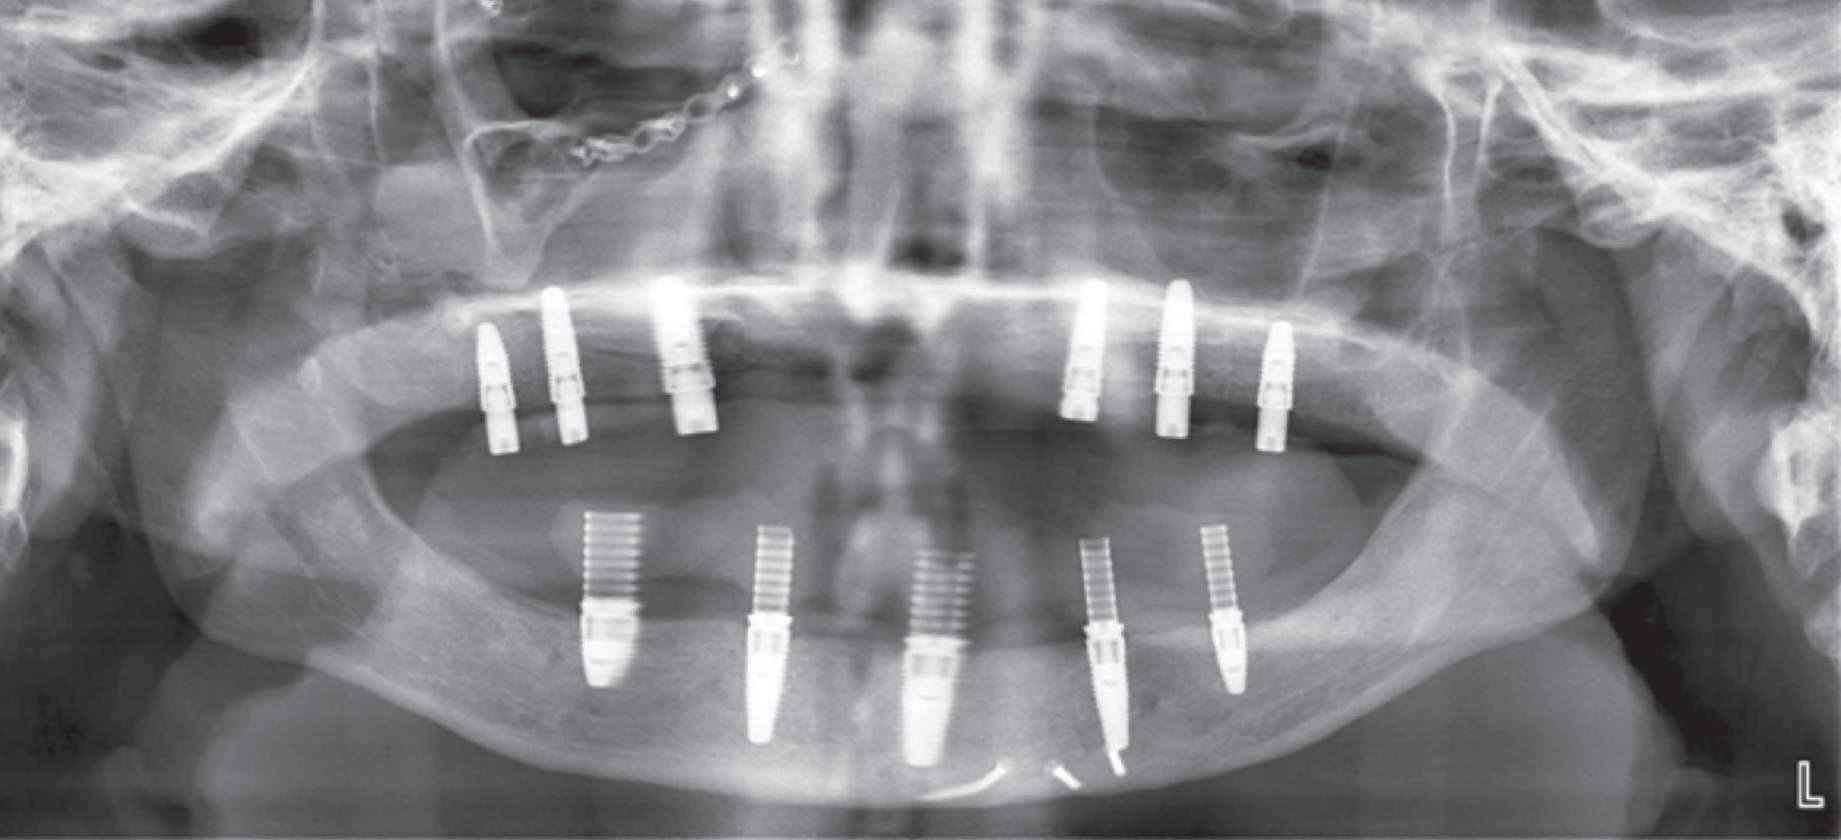

Reabilitările implantare complexe pot include abordări în etape, implicând de obicei extracţia seriată a dinţilor irecuperabili. Se evită astfel necesitatea protezelor mobilizabile prin menţinerea dinţilor naturali în cursul vindecării şi împiedică încărcarea imediată a implanturilor plasate în osul grefat. Un dezavantaj major constă în recesia gingivală. Acest articol dezbate diverse abordări pentru gestionarea modificărilor gingivale şi sugerează modificări de protocol în cursul fazei de planificare terapeutică cu implanturi.

Deşi poate varia de la pacient la altul, acest tip de tratament implică de obicei stadii multiple de inserare a implanturilor în cursul cărora dinţii reziduali dar irecuperabili sunt menţinuţi ca bonturi temporare pentru a susţine restaurări provizorii fixe. Odată cu realizarea conexiunii dintre bonturi şi primul set de implanturi, dinţii reziduali se extrag şi se efectuează o a doua etapă de inserţie a implanturilor. După vindecarea celui de-al doilea set sau a setului final de implanturi, se pot realiza procedurile protetice pe implanturi pentru a finaliza terapia. Cavallaro & Greenstein au împărţit acest protocol în două clasificări: clasa I, cu toate implanturile inserate în cursul primei etape chirurgicale; şi clasa a II-a cu două sau mai multe etape de inserare a implanturilor pentru a genera suficientă susţinere implantară.

Pacientul prezenta dentiţie maxilară şi mandibulară eşuată datorită cariei secundare provocată de xerostomia post-iradiere. Pacientul suferise o disecţie cervicală radicală pentru înlăturarea carcinomului cu celule scuamoase la nivelul gâtului cu 9 ani înainte, urmată de radioterapie dar fără limită de ecranare. S-a utilizat o abordare stadializată pentru a evita protezele mobilizabile pe ţesuturile moi, extrem de uscate. Pacientul a optat pentru tratarea prioritară la nivel mandibular.

Fig. 9 prezintă bonturile de vindecare adiacente dinţilor naturali menţinuţi temporar, iar fig. 10 bonturile individualizate din prima etapă, inserate cu un contur gingival relativ bun şi fără recesie. Recesia era clar vizibilă în jurul tuturor bonturilor din prima etapă, după extracţiile adiacente şi plasarea implanturilor din a doua etapă (fig. 11). Atitudine: S-a decis îndepărtarea acestor bonturi şi amprenta corpului implantar al tuturor implanturilor astfel încât bonturile noi şi cele din prima etapă să fie frezate împreună pentru paralelism şi poziţionarea adecvată a marginii gingivale. Întrucât aceasta necesita îndepărtarea bonturilor din prima etapă care menţineau proteza provizorie, înainte de îndepărtarea tuturor bonturilor individualizate s-au plasat bonturi provizorii, cu scopul de a asigura poziţionarea adecvată şi dimensiunea verticală a restaurării provizorii. Aceste bonturi provizorii au menţinut apoi restaurarea temporară,

Cazul (3): Refrezarea bonturilor individualizate

Figurile

9. Bonturile de vindecare.

10. Bonturile individualizate în prima etapă.

11. Recesia evidentă în jurul bonturilor din prima etapă, după extracţiile adiacente şi inserarea implanturilor din faza a doua.

12. Bonturile refrezate şi noile bonturi individualizate.

în timp ce toate bonturile individualizate au fost fabricate şi/sau frezate în laborator. Fig. 12 prezintă plasarea bonturilor refrezate (la implanturile din prima etapă) şi bonturile individualizate noi (la cele din a doua etapă).